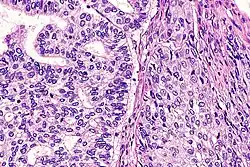

| Micrograph of an adenosquamous carcinoma of the lung. The adeno- or glandular component is on the left of the image and the squamous component on the right of the image. H&E stain. | |

Light microscopy shows a combination of gland-like cells and squamous epithelial cells.[4] On immunohistochemistry, it is typically positive for CK5/6, CK7 and p63, and negative for CK20, p16 and p53. On genetic testing, KRAS and p53 are typically altered.[4]